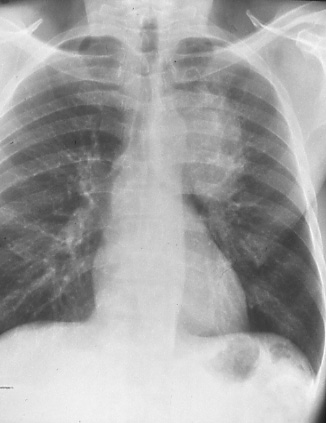

Fig. 16a: Posterior-anterior chest radiograph shows a large central bronchogenic carcinoma on the left; questionable involvement of mediastinum or vascular structures, T3 or T4.